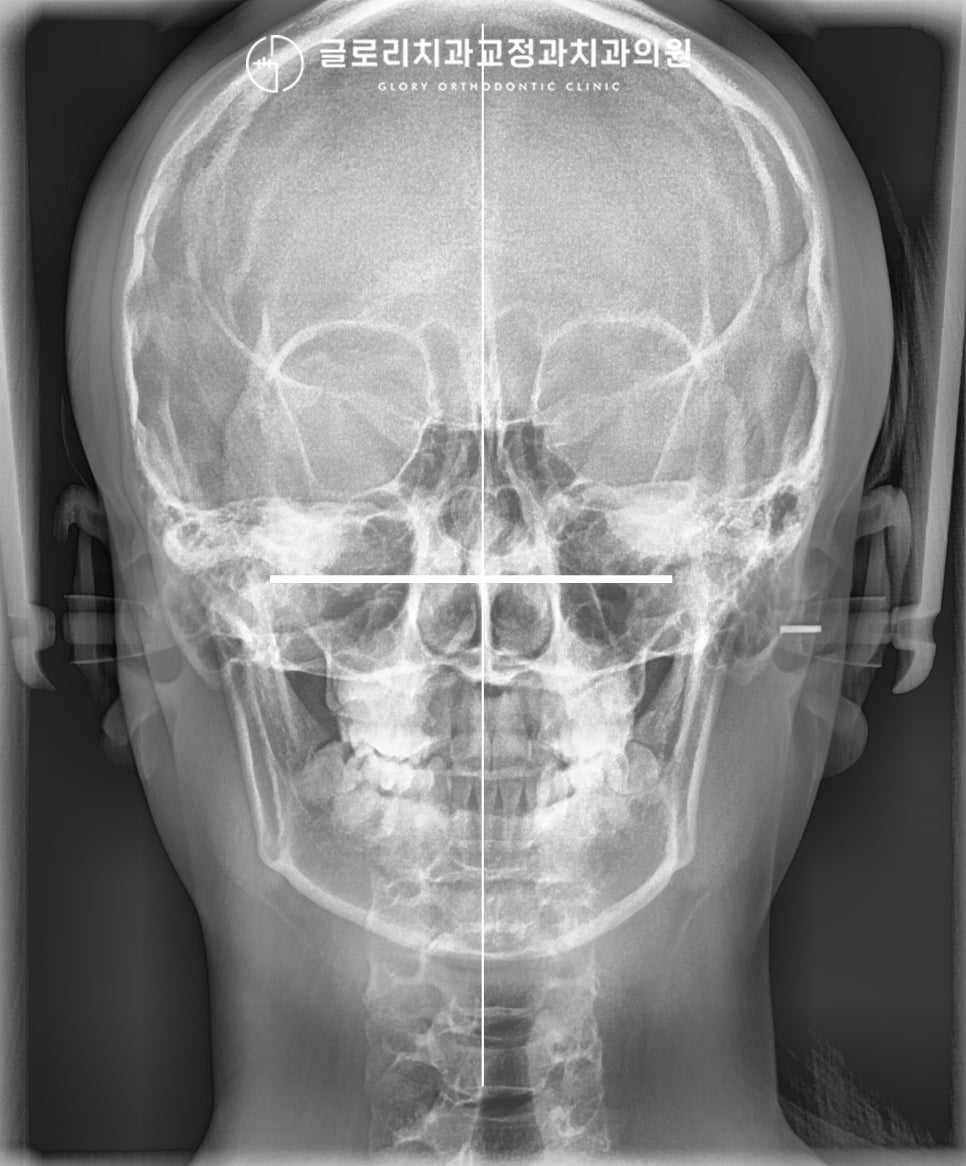

정면 엑스레이에서도 마찬가지로

턱 끝이 왼쪽으로 편위 되어 있습니다.